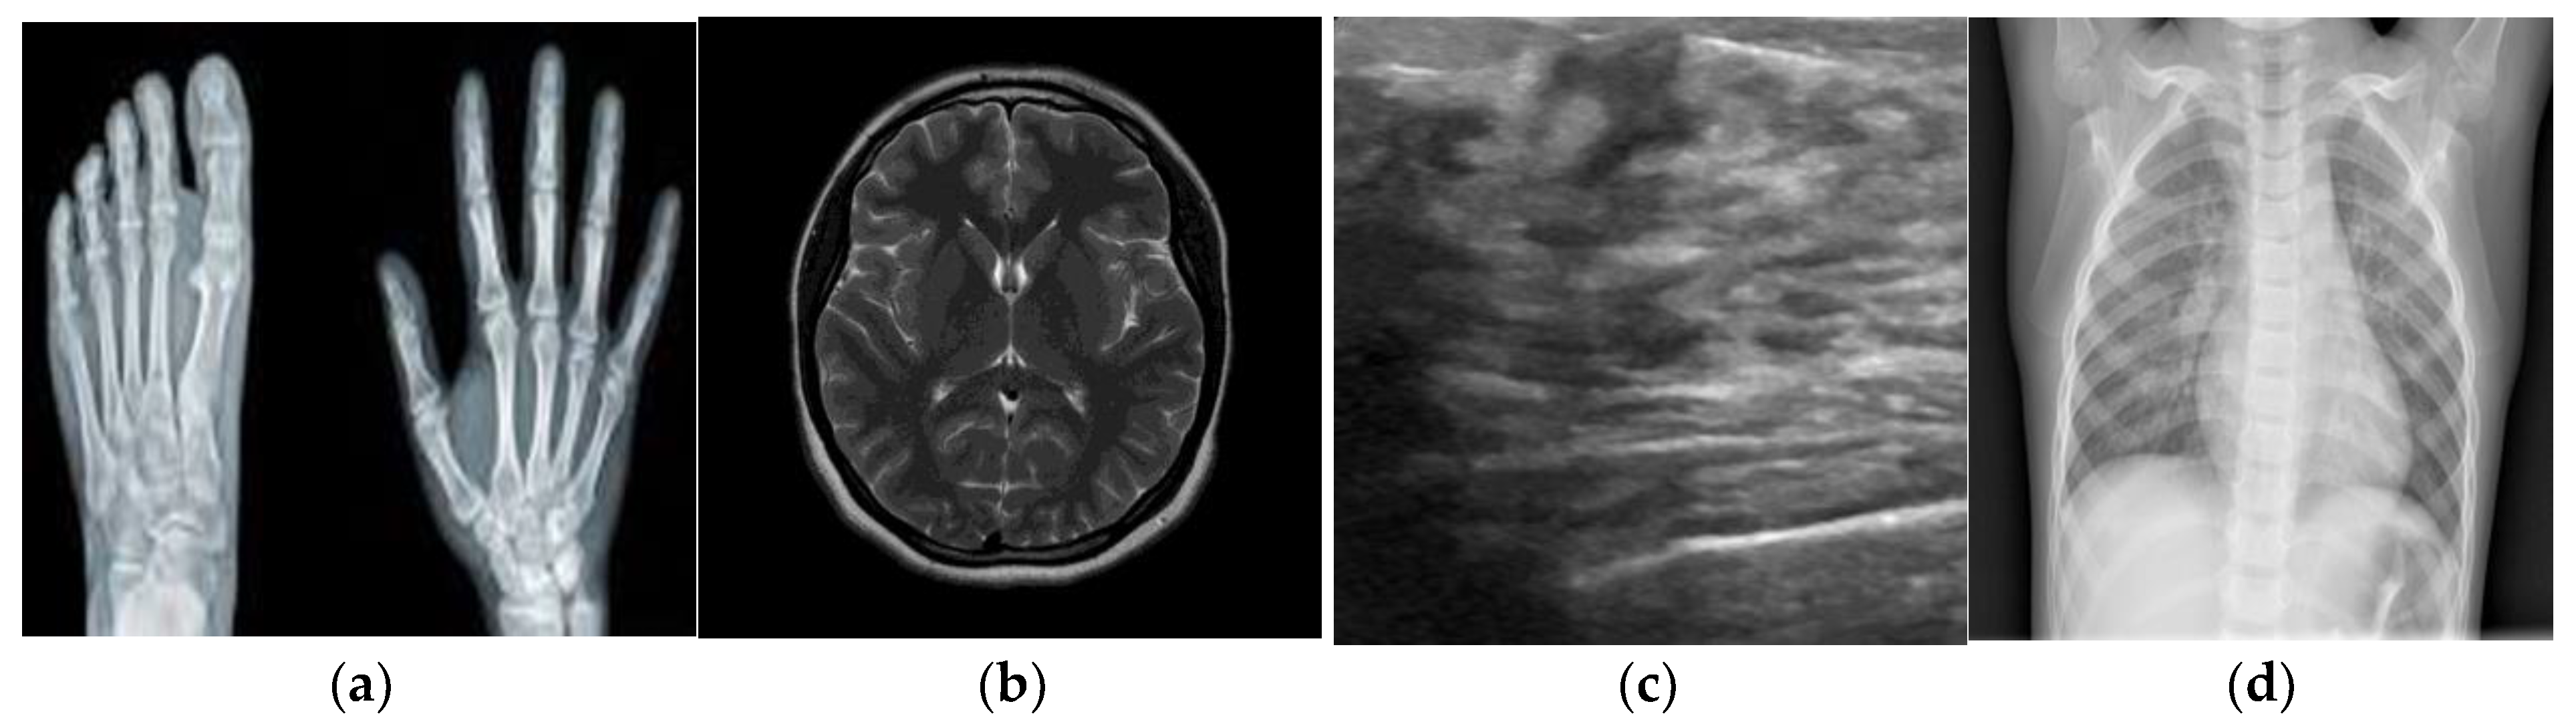

To test the robustness with standard grayscale medical images, palm X-ray, brain tumor, ultrasound, and chest X-ray images of size 256 × 256 are considered as the experimental images, as shown in Figure 8.

Figure 8.

(a) Palm X-ray; (b) brain tumor; (c) ultrasound; (d) chest X-ray.